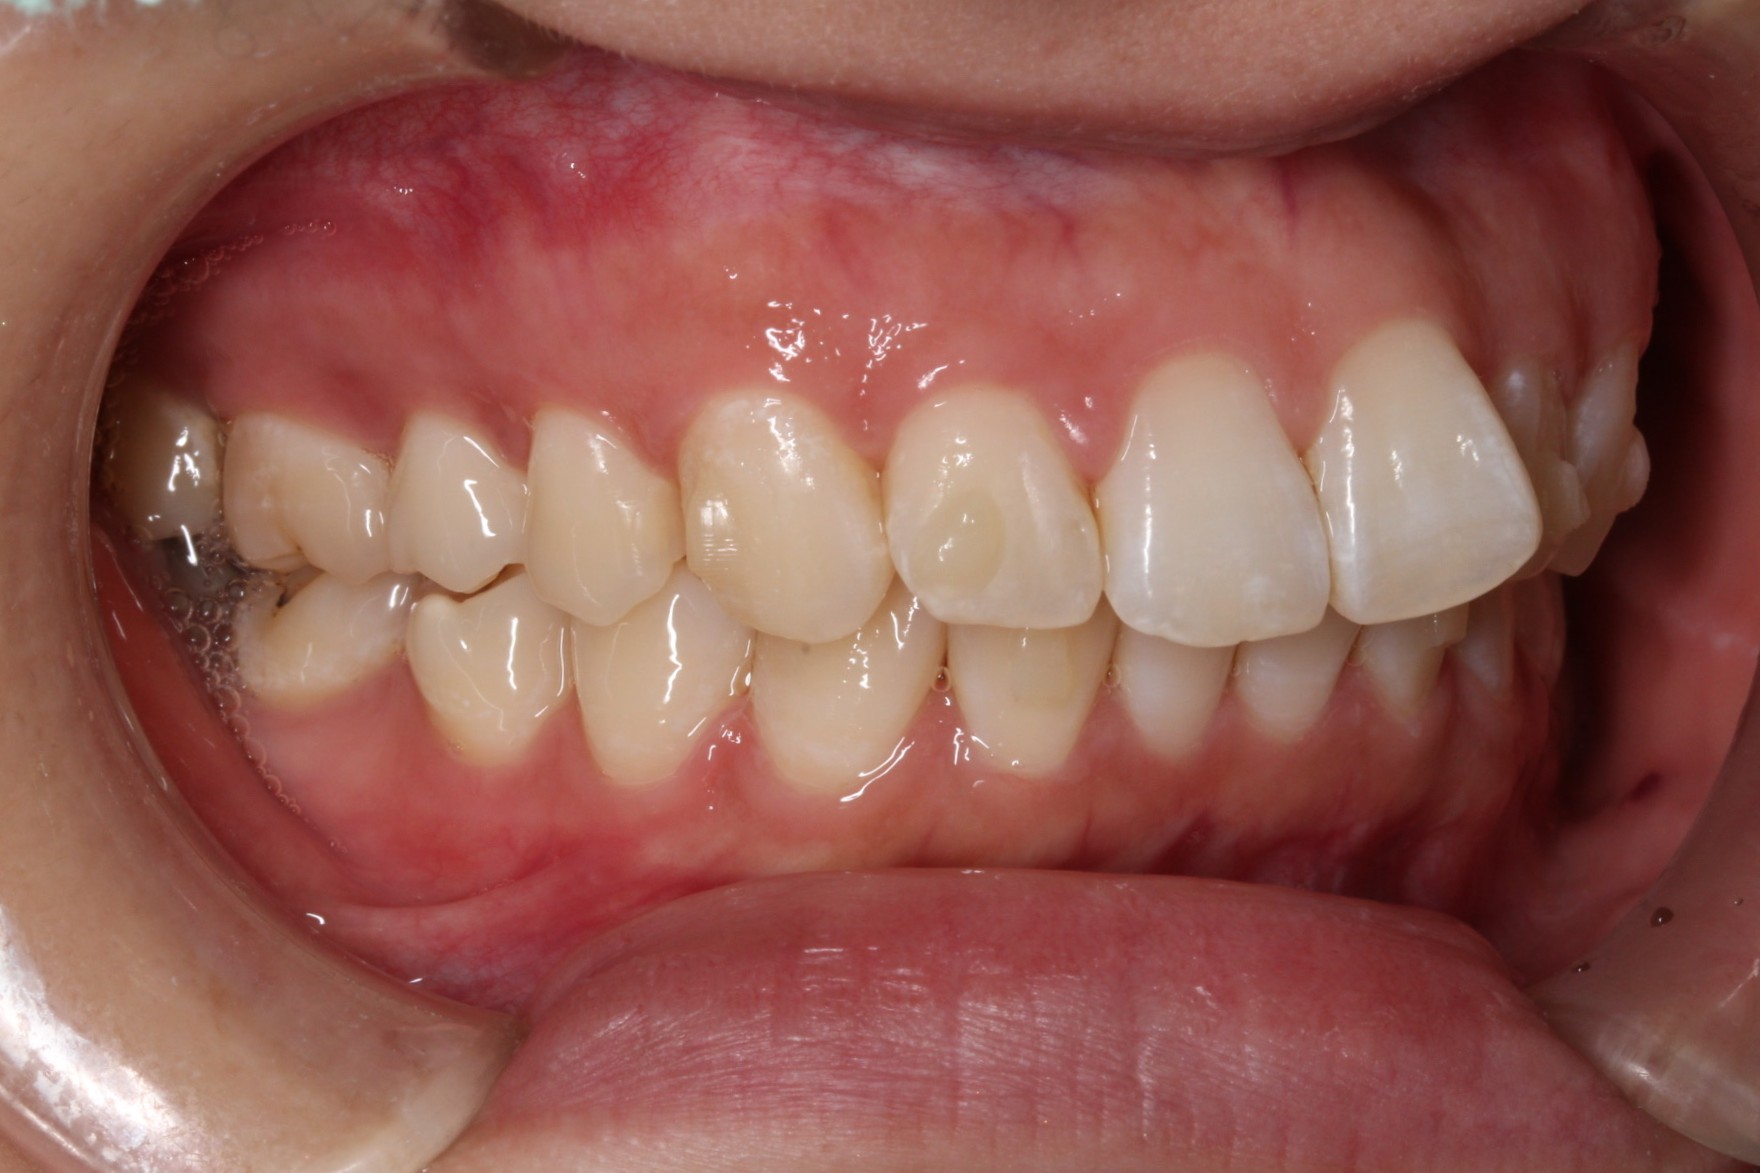

矯正術前:右側

矯正術後:右側